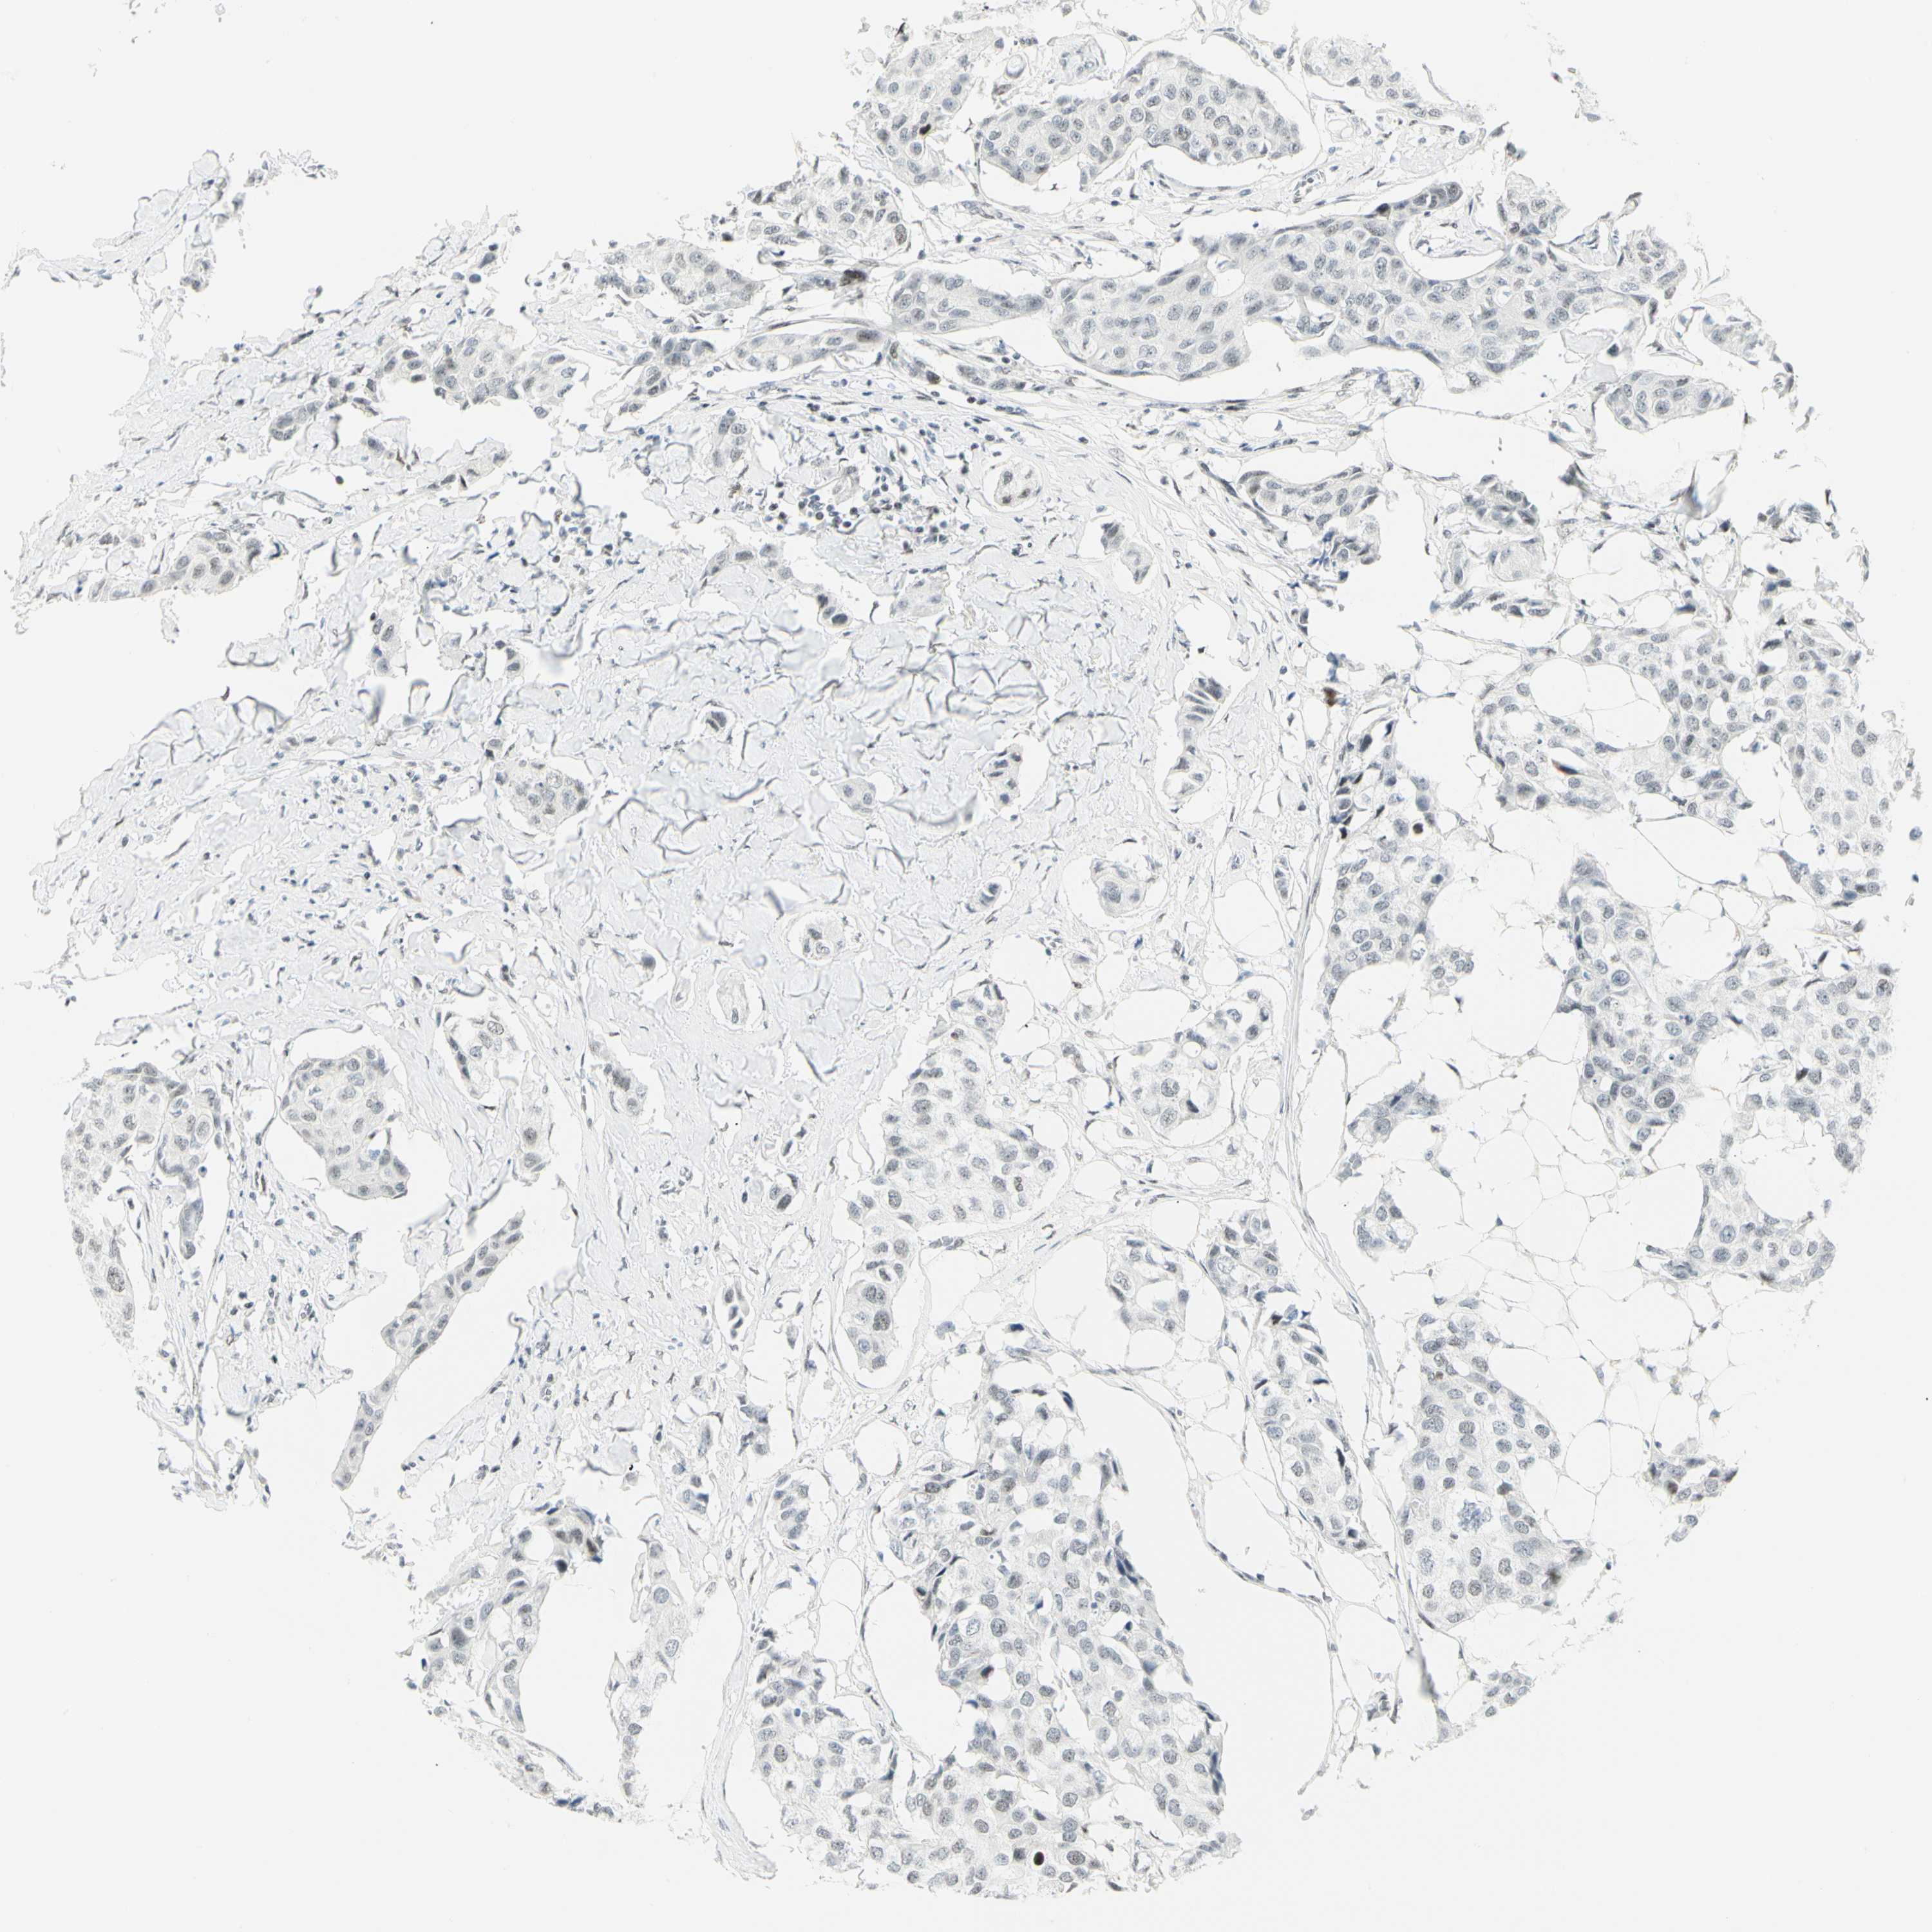

CANCER BREAST CANCER Show tissue menu

BRCA TCGA BRCA VALIDATION PROTEIN EXPRESSION